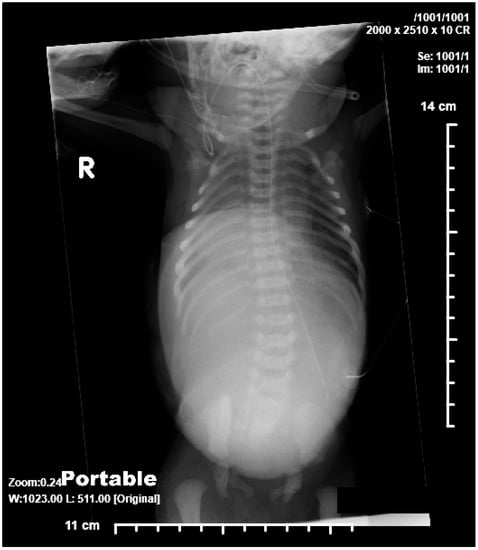

2.2. Case 2